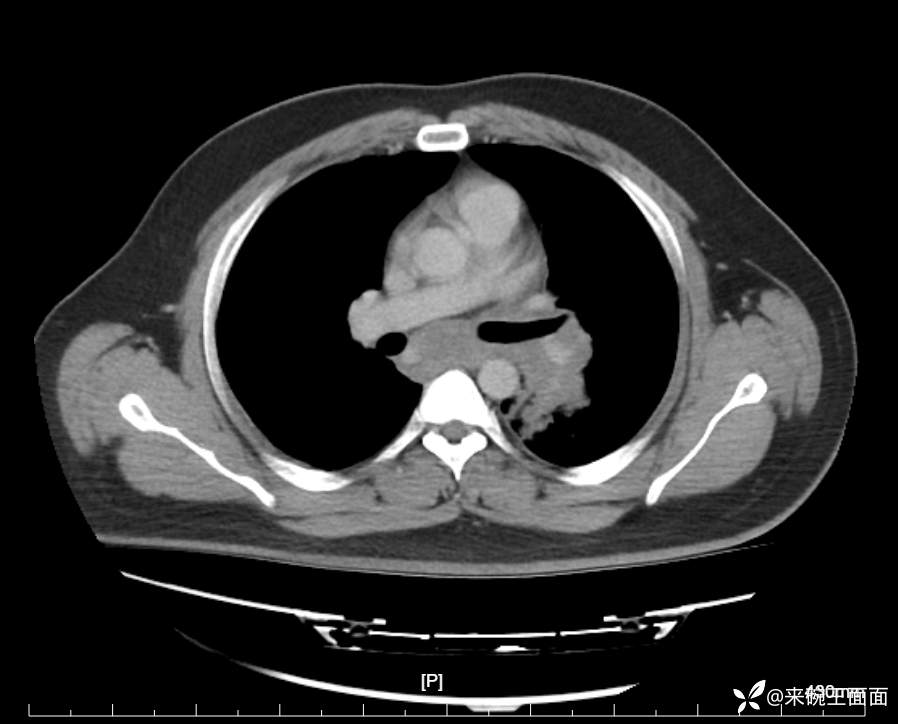

性别:男

年龄:27岁

主诉:胸闷胸痛数月余,休息后可自行缓解,无咯血症状。

个人史:数年吸烟史,具体不详。